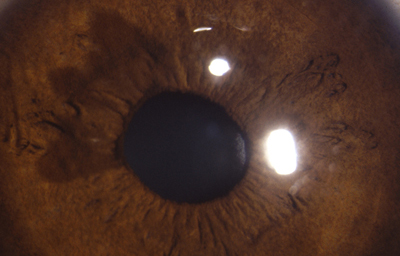

Policoria falsa en midriasis OI: sinequia en el borde pupilar temporal con banda fibrosa 3 a 4; se ve el collarete y el esfínter periféricos a la pequeña pupila, lineas de tracción superiores e inferiores hacia el puente que separa las 2 aperturas de la 1 a las 5 - dentro de apertura pequeña, parece existir un remanente de membrana pupilar.

Archivo Fotográfico Dr. Carmen Barraquer. 1983